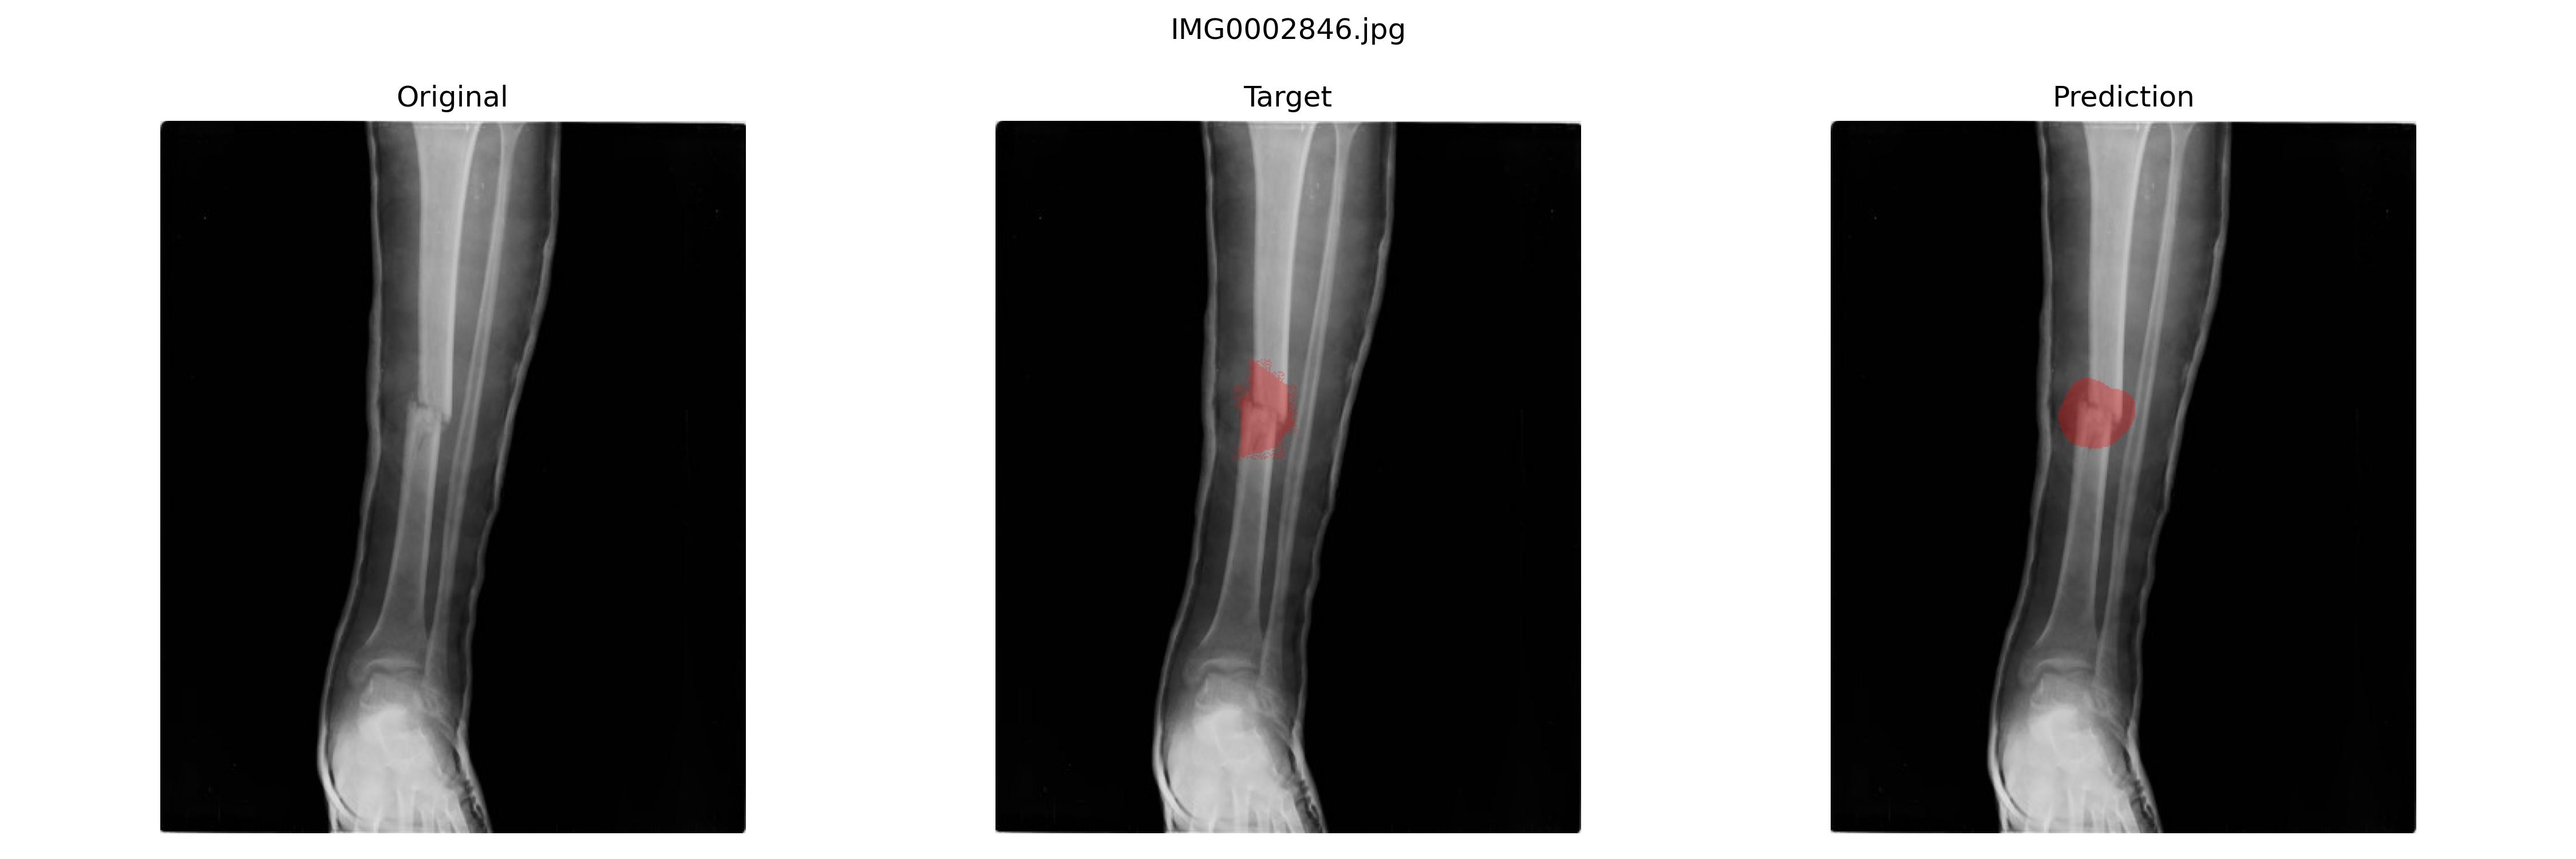

最佳模型是

epoch:110,sensitivity(Recall):0.3831927899240895,specificity:0.9985073638473289,precision:0.6006053270923088

好的结果

不好的结果

最后结果并不是很好,并且换了U-net以及加权交叉熵损失、Dice损失之类的之后也一样,我认为和这个数据集的标注逻辑有关。骨折的地方就那个断面,周围标注可大可小,这种应该比较适合bbox标注做目标检测。